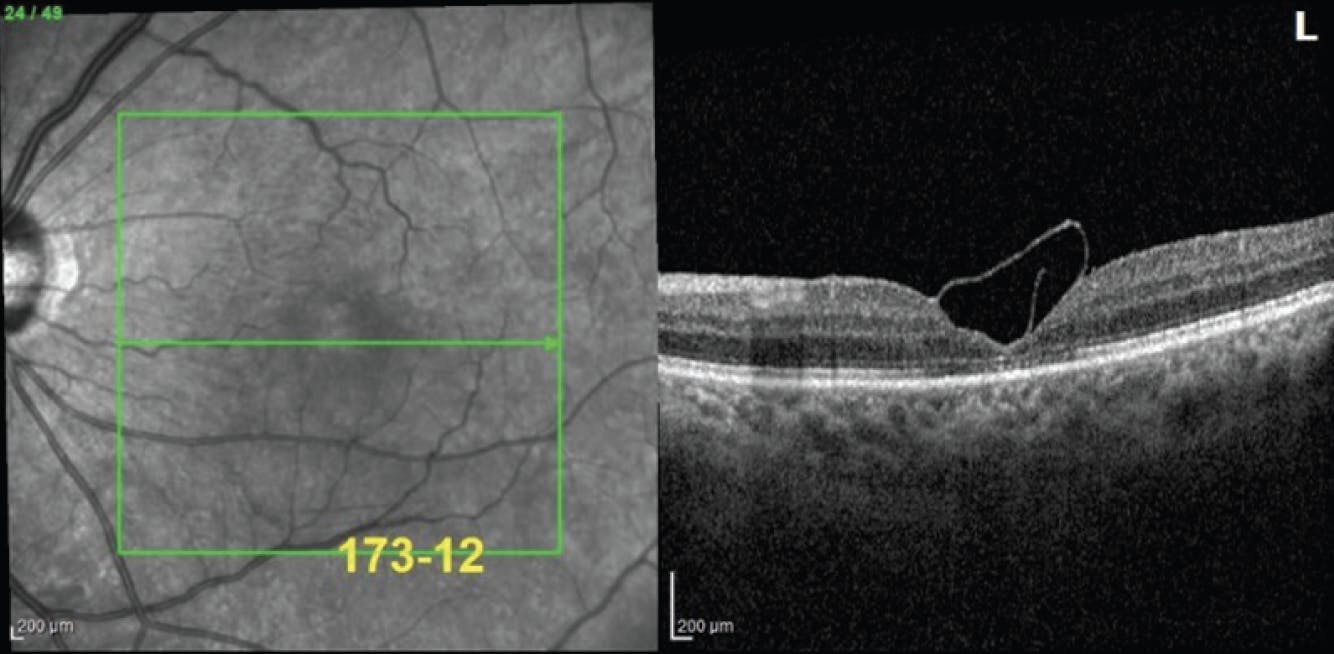

<p>Figure 1. OCT documented a chronic FTMH prior to treatment with the inverted ILM flap technique.</p>

Figure 1. OCT documented a chronic FTMH prior to treatment with the inverted ILM flap technique.